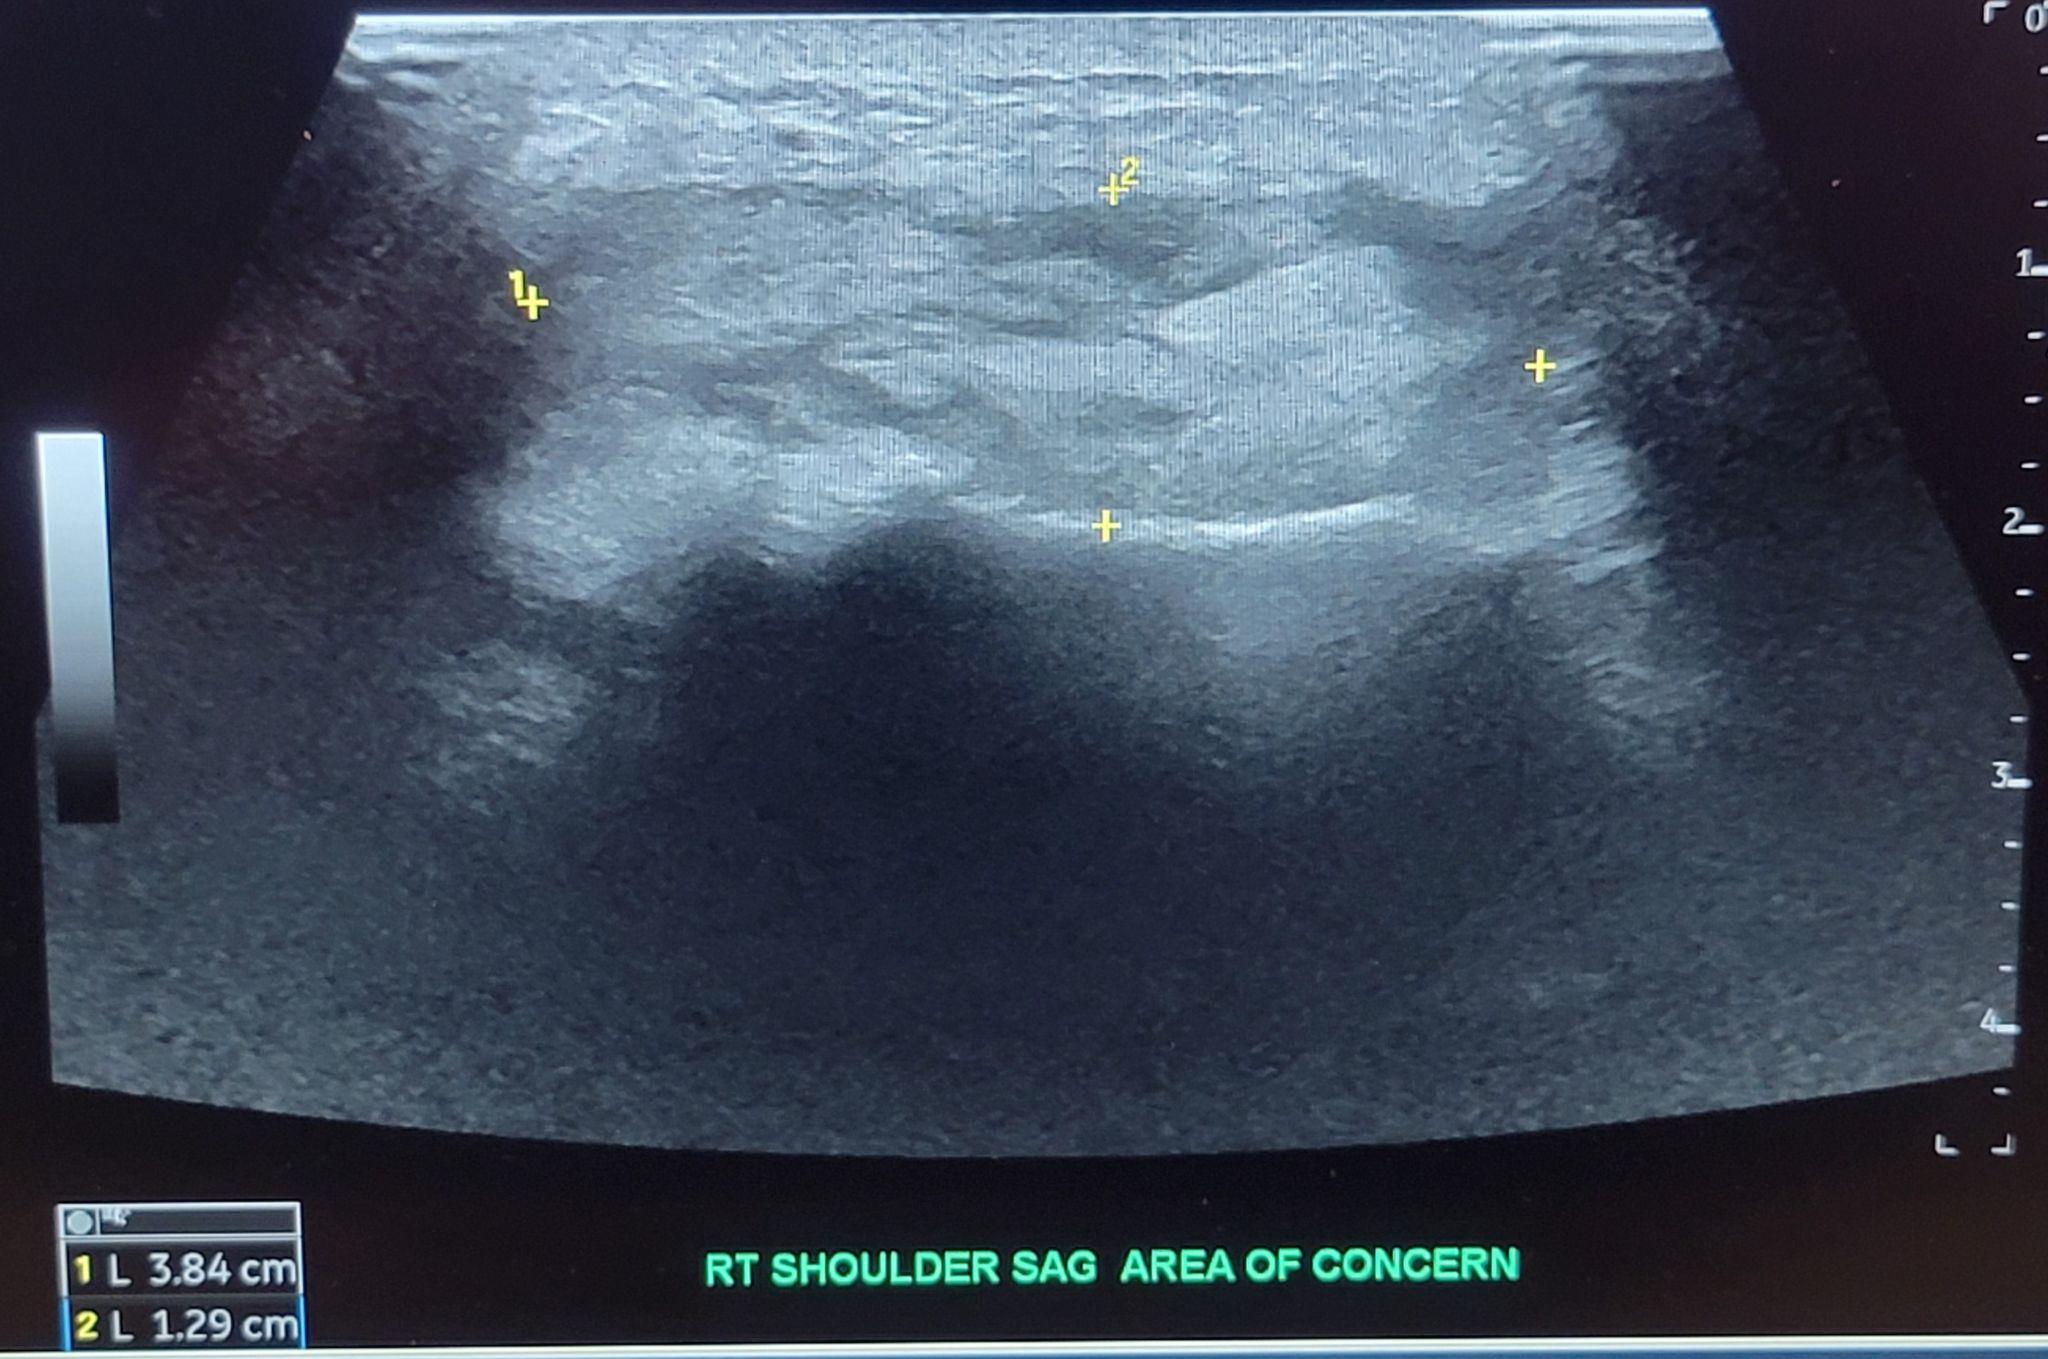

Infectious disease became a concern as the patient continued to have an upward trending white blood cell count and continued pain despite antibiotics on the fourth day. The recommendation for STAT MRI as well as orthopedic re-evaluation for possible surgical exploration was given. The next day, orthopedics did not wish to explore surgically as previous imaging did not reveal any signs of necrotizing disease or obvious fluid collection. The repeat MRI with contrast resulted after the initial orthopedic evaluation was concerning for septic arthritis as well as osteomyelitis of the acromion and distal clavicle [Figure 1]. Additional ultrasound imaging was ordered and confirmed a 1.3cm x 2cm area of fluid collection [Figure 2]. Interventional radiology was again consulted but was unable to perform arthrocentesis as there was no clear uncontaminated path due to overlying cellulitis. The decision was made for incision and drainage for the next morning [Figure 3].

The patient was examined with a multitude of imaging modalities during his course. Initial x-ray radiographs along with CT imaging with contrast in the emergency department did not reveal any fluid collection or signs of osteomyelitis. The initial MRI was performed without contrast and also did not demonstrate a drainable fluid collection. Only after six days of admission and re-imaging of the shoulder with contrast-enhanced MRI was their evidence of septic arthritis which was even more accurately characterized by ultrasound. It cannot be known if a bedside ultrasound in the emergency department would have identified the fluid collection as it is unknown whether it had manifested at the time of examination given the negative results of both CT and MRI imaging, however, is an area that may warrant further exploration.7 Interventional radiology was consulted initially and was unable to perform the arthrocentesis as during their review there was not a drainable collection. Fortunately for our patient, the interventional radiologist was unable to find an uncontaminated path for arthrocentesis secondary to overlying cellulitis. The availability, improved accuracy, and safety of interventional radiology performing this procedure have made it a preferred approach, however, this may lead to delays in diagnostics and treatment.8 Without surgical exploration, the tract between the purulent fluid collection and clavicle would have likely not been identified and led to a prolonged, difficult course and possibly deadly outcome.